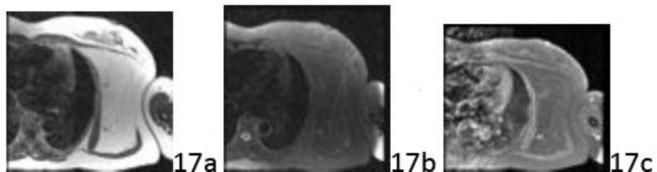

Question 17 An otherwise healthy 52-year-old man has had a several year history of a slowly enlarging, symptomatic left shoulder, axillary, and chest wall mass.

Radiographs are only remarkable for a large soft-tissue mass. Selected sequences of MRI scans are shown in Figure 17a (T1), Figure 17b (T2 fat saturated), and Figure 17c (T1 fat saturated post-gadolinium). Management of this symptomatic mass should consist of which of the following?

Question 17 An otherwise healthy 52-year-old man has had a several year history of a slowly enlarging, symptomatic left shoulder, axillary, and chest wall mass.

Radiographs are only remarkable for a large soft-tissue mass. Selected sequences of MRI scans are shown in Figure 17a (T1), Figure 17b (T2 fat saturated), and Figure 17c (T1 fat saturated post-gadolinium). Management of this symptomatic mass should consist of which of the following?

1. ## Forequarter amputation

2. ## Wide resection, chemotherapy, and radiation therapy

3. ## Wide resection and radiation therapy

4. ## Marginal excision

5. ## Incisional biopsy

DISCUSSION: The MRI scans show a large soft-tissue mass that is iso-intense with subcutaneous fat of all sequences. This is diagnostic of a lipocytic (fatty) tumor-either lipoma, atypical lipomatous tumor, or low-grade liposarcoma. As such, no biopsy is necessary because biopsies of these fatty tumors can be fraught with sampling error. The most appropriate treatment of this symptomatic lesion is simple, marginal excision without radiation therapy or chemotherapy. Local recurrence can occur in 25% to 50% of patients at 10 years. Dedifferentiation is rare with subsequent recurrent disease; but when it occurs, it may result in metastases. The Preferred Response to Question # 17 is 4.

1. ## Forequarter amputation

2. ## Wide resection, chemotherapy, and radiation therapy

3. ## Wide resection and radiation therapy

4. ## Marginal excision

5. ## Incisional biopsy

DISCUSSION: The MRI scans show a large soft-tissue mass that is iso-intense with subcutaneous fat of all sequences. This is diagnostic of a lipocytic (fatty) tumor-either lipoma, atypical lipomatous tumor, or low-grade liposarcoma. As such, no biopsy is necessary because biopsies of these fatty tumors can be fraught with sampling error. The most appropriate treatment of this symptomatic lesion is simple, marginal excision without radiation therapy or chemotherapy. Local recurrence can occur in 25% to 50% of patients at 10 years. Dedifferentiation is rare with subsequent recurrent disease; but when it occurs, it may result in metastases. The Preferred Response to Question # 17 is 4.